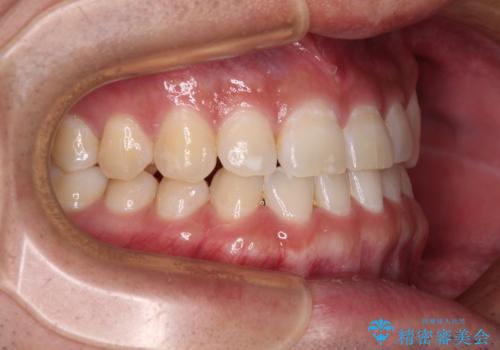

隙間の空いた前歯を治したい 上顎の部分矯正

- 上顎前歯の隙間を気にして来院された患者様です。

下顎前歯に叢生がありましたが、特に気にしていらっしゃいませんでした。

下顎臼歯にインプラント補綴治療がされており、全顎治療するにはクラウンの作り替えが必要となる旨を説明し、ワイヤー装置により上顎のみの矯正治療を行うこととしました。